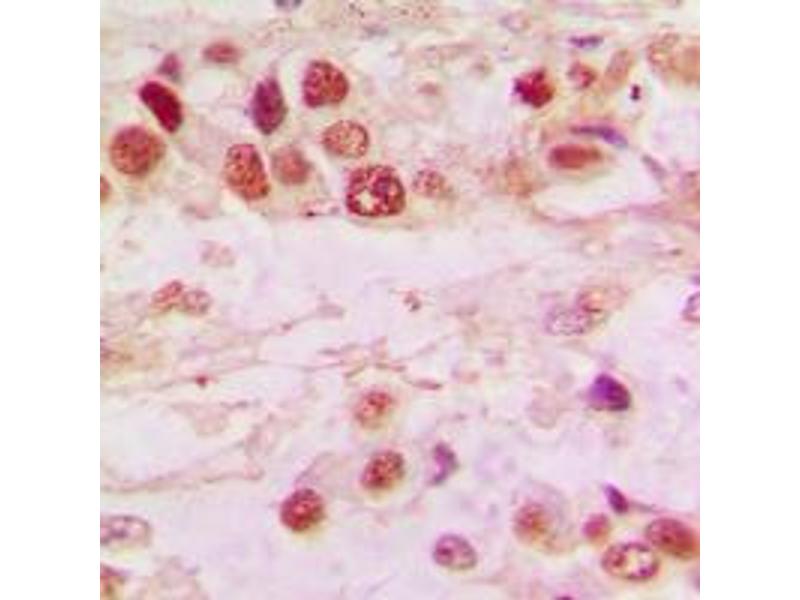

HDAC7 Reactivité: Humain WB, ELISA, IHC, IHC (p) Hôte: Lapin Polyclonal FITC

N° du produit ABIN2605590

678,59 €